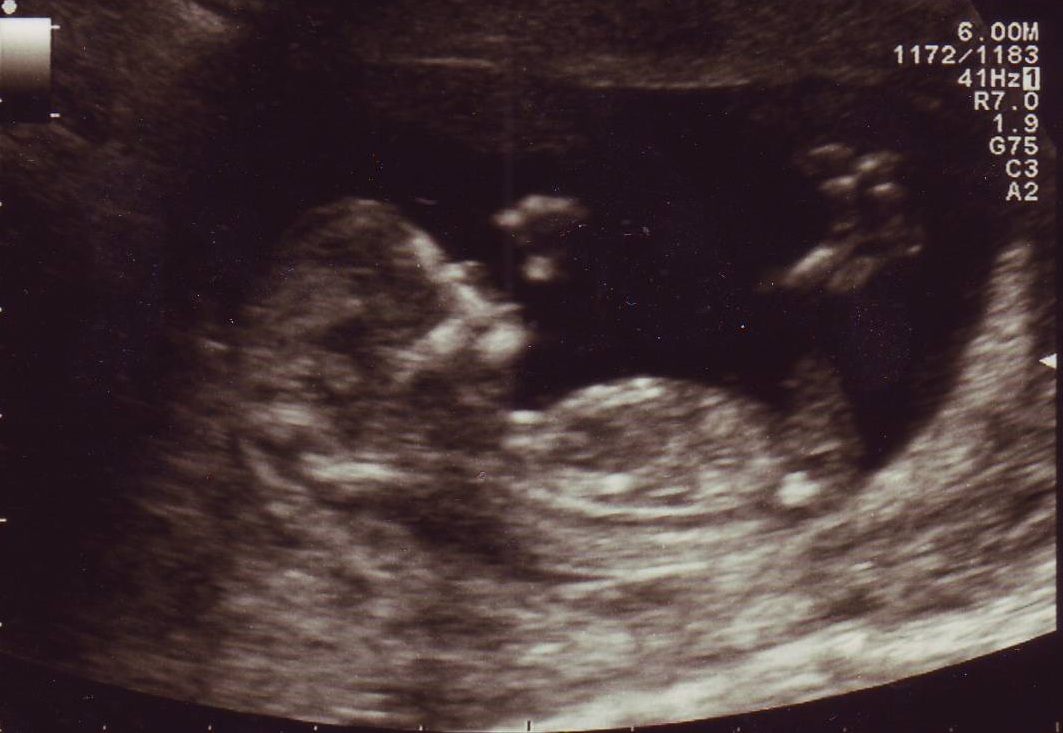

Attachment 7791Here is another pic fom same day, i know there is no nub visable but any ideas on the skull theory?:think:

Im thinking it looks a little boyish

I thought the 2nd pic looked boyish too.

Slight boy lean but I hope I'm wrong!